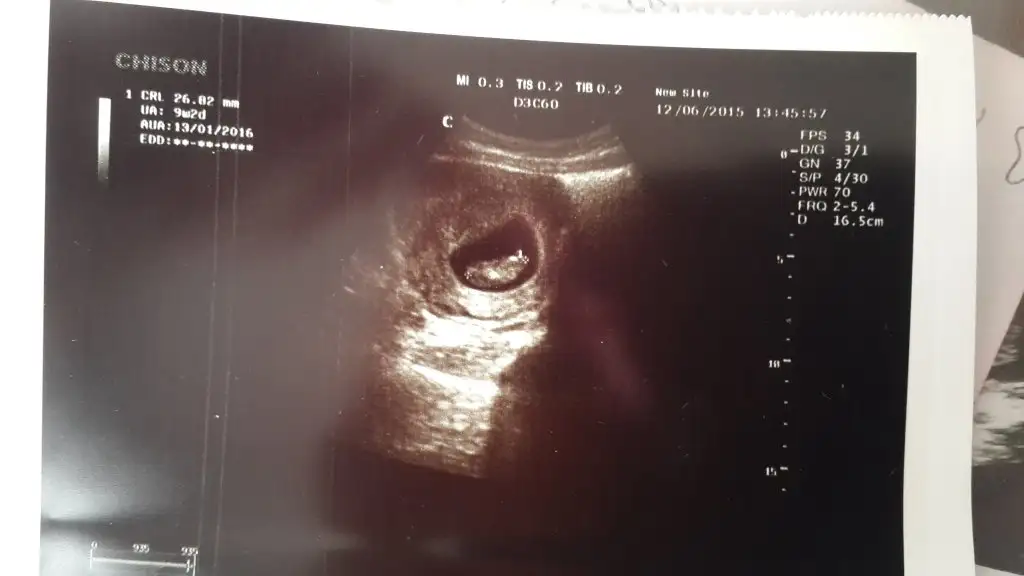

Selam kızlar, şimdi doktordan geliyorum. saolsun doktorum o kadar ruhsuz ki zorla kaç gr kaç cm onu sordum söledi ki sölediği değerle ultrasonda yazan değer farklı. bana 6 cm diyo ama ultrason kağıdında 3,75 cm yazıyo içimi şişirdi resmen eli oluşmuş ayağı var bile demedi ben ultrason kağıdınn içine düşeceğim birazdan ( sanki çok anlıyorum ya ).

15 gün önce gittiğiden beri 2 gün geride görünüyo yani 2 hafta içinde eksik mi gelişmiş :110: anlayamadım doktor önemli değil ddi ama ona güvenmediğimden size danışayım dedim.